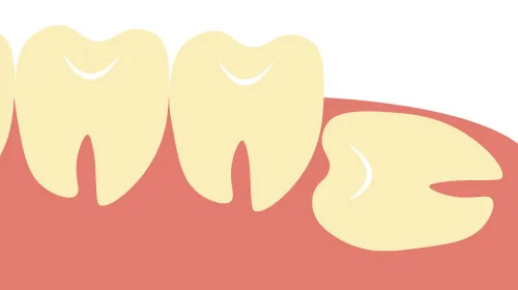

親知らずが深い、横向きに埋まっているなど、通常は大学病院等の専門機関へ紹介となることが多い症例でも、状態を確認のうえ当院で対応を提案できます。必要に応じてレントゲンやCTで神経の位置も確認し、安全性を優先して計画します。

横向きに生えている場合

埋まっている場合